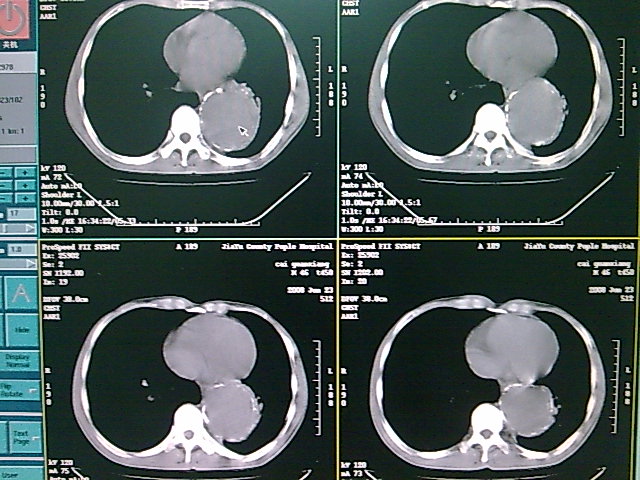

以下是引用dyqct在2008-6-27 14:37:00的发言:[br]支持胸主动脉瘤,建议增强进一步检查。

以下是引用zsl6918在2008-6-27 14:24:00的发言:[br]动脉瘤